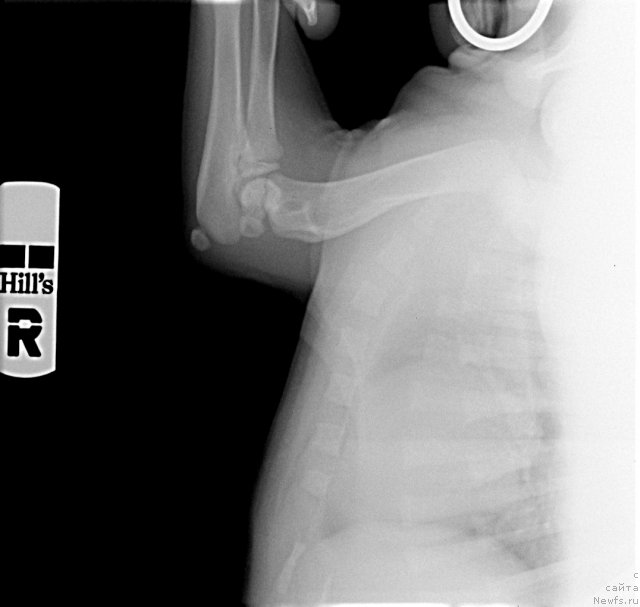

А это рентген суставов месячного щенка.

Фотография № 116297